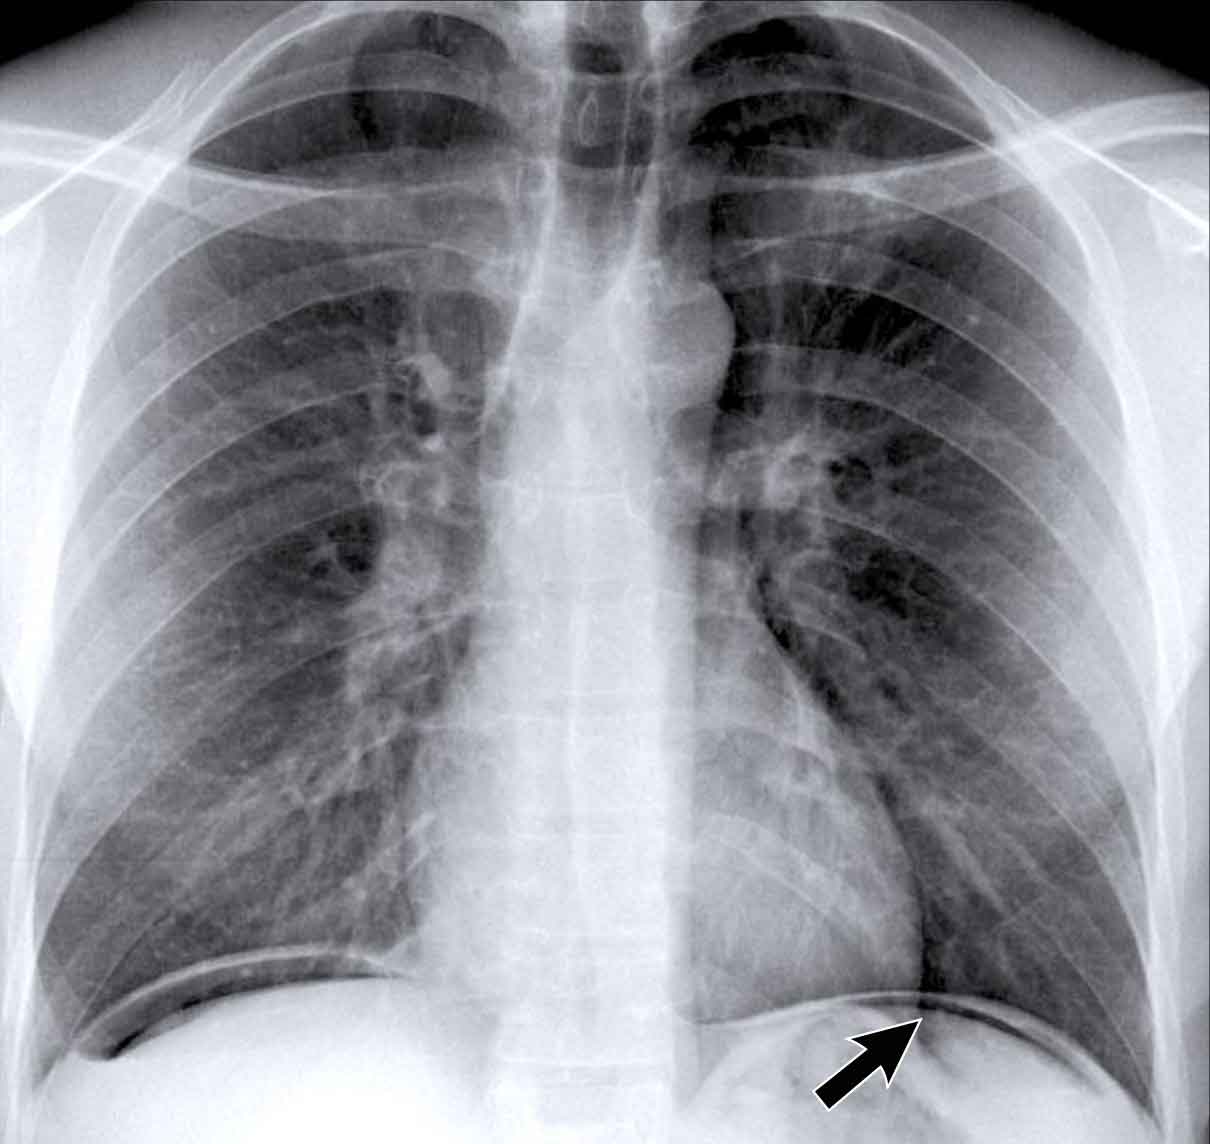

Hidden Areas (3): Pneumonia Below the Diaphragm

In this case, a pneumonia was primarily located below the right diaphragmatic dome (yellow arrow), within the posterior basal segment of the right lower lobe.

• On the lateral view, there is an increase in opacity over the lower thoracic vertebrae, indicating lower lobe consolidation (arrow).

• Again, image magnification may be necessary for adequate assessment.